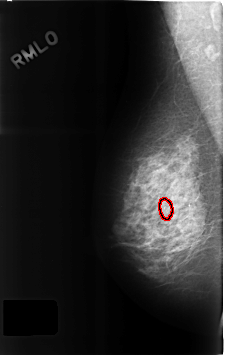

C_0315_1.RIGHT_MLO

RIGHT_MLO LINES 4608 PIXELS_PER_LINE 2920 BITS_PER_PIXEL 12 RESOLUTION 50 OVERLAY

FILE: C_0315_1.RIGHT_MLO.OVERLAY

TOTAL_ABNORMALITIES 1

ABNORMALITY 1

LESION_TYPE CALCIFICATION TYPE PLEOMORPHIC DISTRIBUTION CLUSTERED

ASSESSMENT 4

SUBTLETY 4

PATHOLOGY BENIGN

TOTAL_OUTLINES 1

BOUNDARY